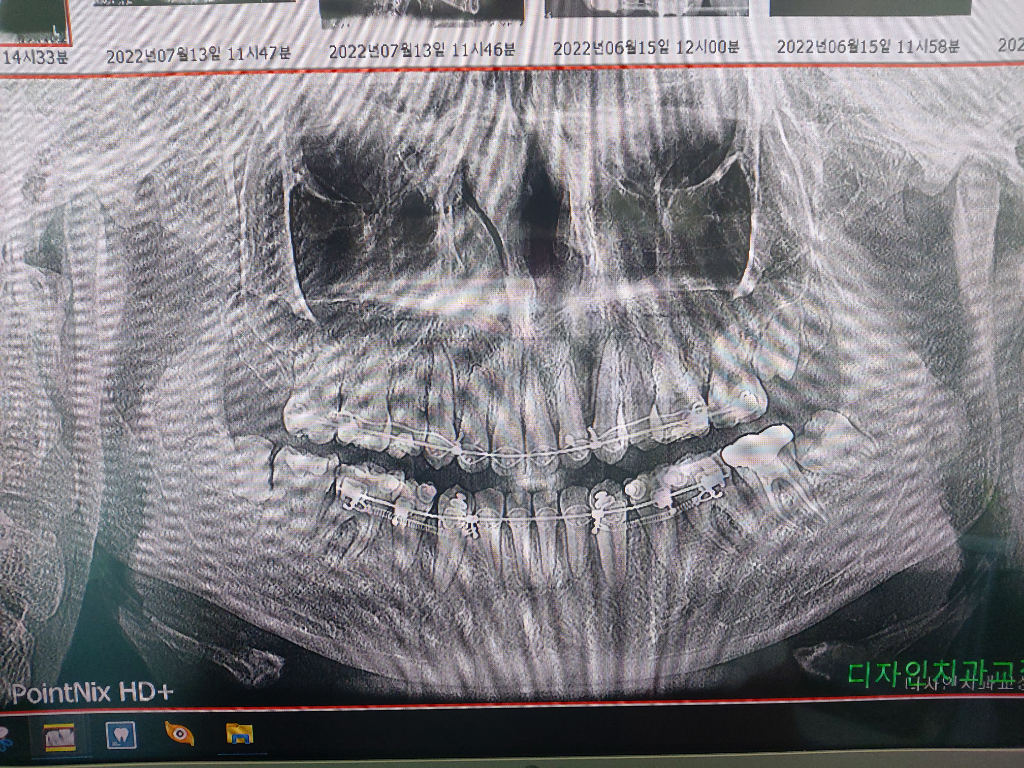

교정 중에 사랑니가 났는데 꼭 뽑아야하나요?

교정중인데 사랑니가 3개가 났는데 두개가 반매복이고 하나는 다른 치아처럼 1자로 났어요. 아프지도 않고 별 증상고 없어서 사랑니가 난 것도 몰랐어요. 근데 치과에서 사랑니를 빼라네요. 꼭 뽑아야하나요? 교정때문에 아파서 밥도 잘 못먹은 적도 몇번 있고 엄헌 이빨도 뽑고 나사도 박고 이런 전적이 있으니까 굳이 뽑어야하나 싶네요

엑스레이 샂ㄴ입니다

• 1번 째 사진